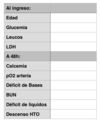

Child pugh

TP

Ascitis

Blr

ALB

Encefalopatia

pour another beer at eleven